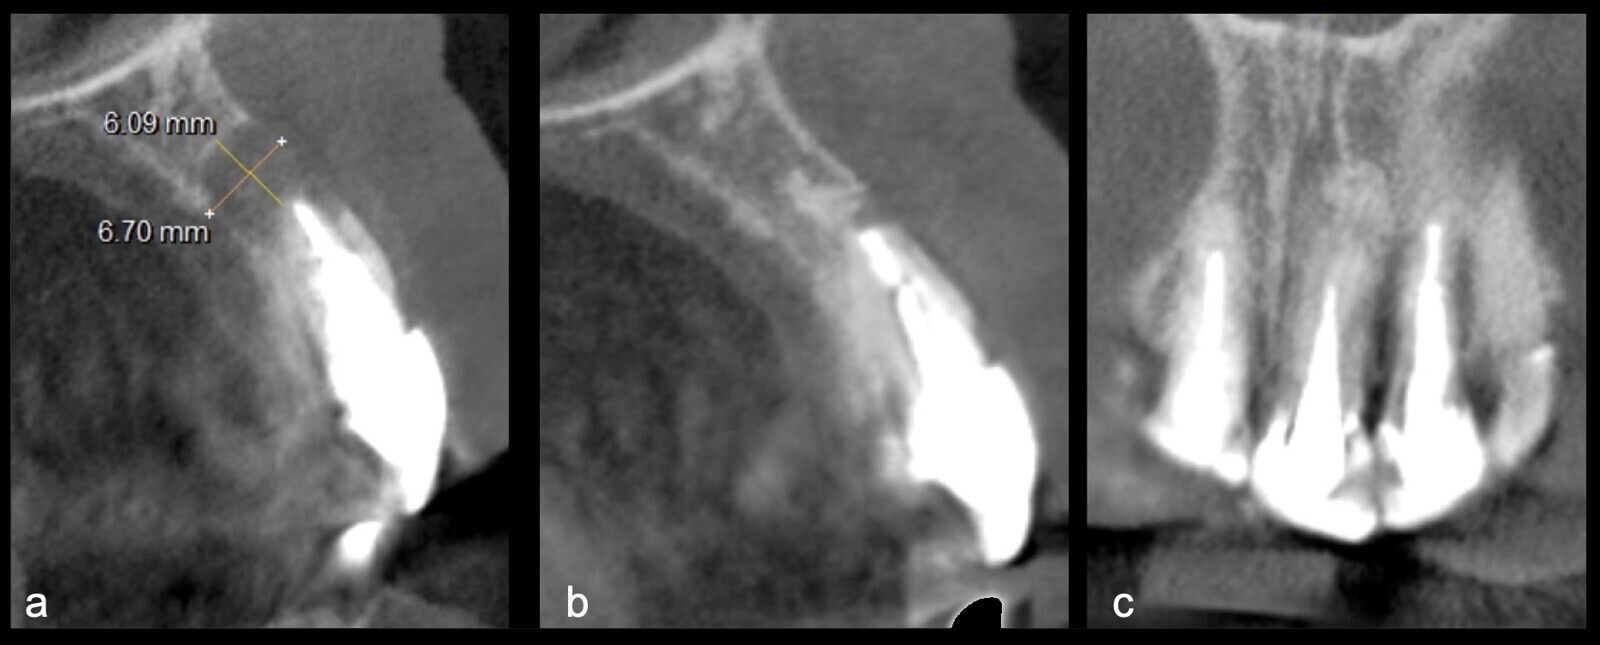

Figura 24. Vista sagital TCCB pieza 2.1. Preoperatorio: imagen hipodensa de 6 mm de diámetro con osteólisis y pérdida de tabla vestibular y palatina (a). Control a los 3 años: imagen hiperdensa compatible con zona regenerada a nivel apical, con presencia de cortical palatina y vestibular (b). Vista coronal TCCB pieza 2.1 control a los 3 años: imagen hiperdensa compatible con hueso en proceso de reparación, presencia de cortical palatina y vestibular (c).